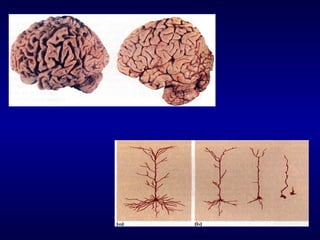

A DOENÇA DE ALZHEIMER

Placas senis

Fusos neurofibrilares